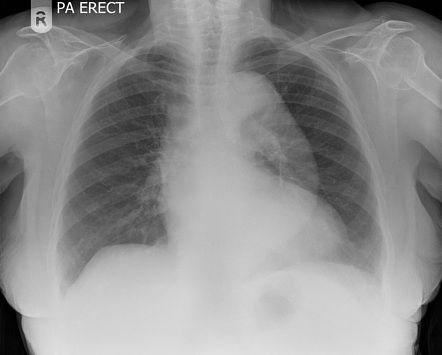

What does loss of definition of right heart border indicate?

Right middle lobe consolidation

What does loss of definition of left heart border indicate?

Lingular consolidation

What does a loss of definition of aortic knuckle indicate?

Aneurysm

What does loss of the aorto-pulmonary window suggest?

Mediastinal lymphadenopathy = malignancy